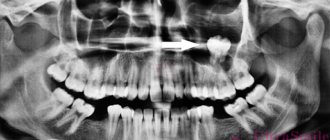

The main reason for the accumulation of thick mucus in the nasal cavity and the appearance of a cyst in it is sinusitis. If a person has a deviated nasal septum or other problems in the structure of the jaws, palate, or maxillary sinuses, then he is at particular risk. In this case, radiography or MRI is used to identify the cyst.

• The main etiological cause of the appearance of maxillary sinus cysts is sinusitis. This condition is usually provoked by an inflammatory process, leading to severe swelling of the mucous membrane. Such conditions are favorable for blockage of the excretory ducts and the formation of a large number of cysts in both the right and left sinuses. If sinusitis is detected, the doctor must conduct a radiological examination.

Before starting treatment for a cyst, it is important to carry out all the necessary diagnostic measures. To do this, it is mandatory to take x-rays and visit an otolaryngologist. After identifying the main cause of the cyst, the doctor prescribes correct and effective treatment. For example, one of the reasons for the appearance of a cyst can be dental disease. After visiting the dentist and eliminating the main cause of the disease, the disease will go away on its own.